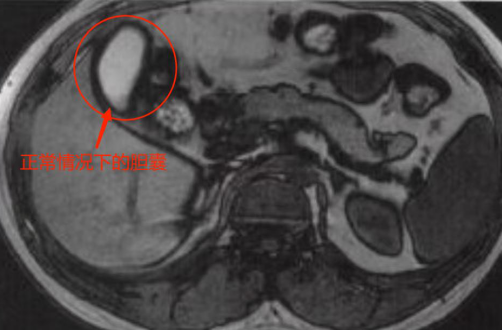

磁共振下正常的胆囊 通讯员 供图

通过检查结果医生判断,小王的腹痛是由急性胆囊炎引起的,而磁共振结果显示,他的胆囊已经肿大到了12.7公分,足足接近正常人胆囊的2倍大小(正常为5~8公分)!同时还伴有局部的腹膜炎。而此时的小王也已经开始出现全身感染的症状,高烧到了38.6,如果不马上进行治疗,极有可能造成感染性休克,随时危及生命。